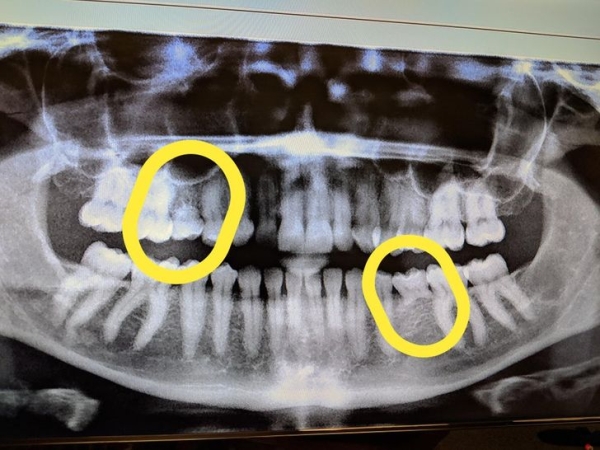

This is a photo of a childs skull shown with adult teeth waiting to protrude and replace baby teeth. Bitewing x-rays are recommended every six to 18 months for a child with an increased risk of tooth decay and every 12 to 36 months for a child at low risk. New born baby teeth xray.

Treatments for congenitally missing teeth. This is a photo of a childs skull shown with adult teeth waiting to protrude and replace baby teeth. Honesty Baby Teeth Xray Meme 2022.

These Photos Show What A Baby S Skull Looks Like When Both The Baby And Adult Teeth Are Present The Adult Teeth Are Forming While The Baby Teeth Are Getting Pushed Out